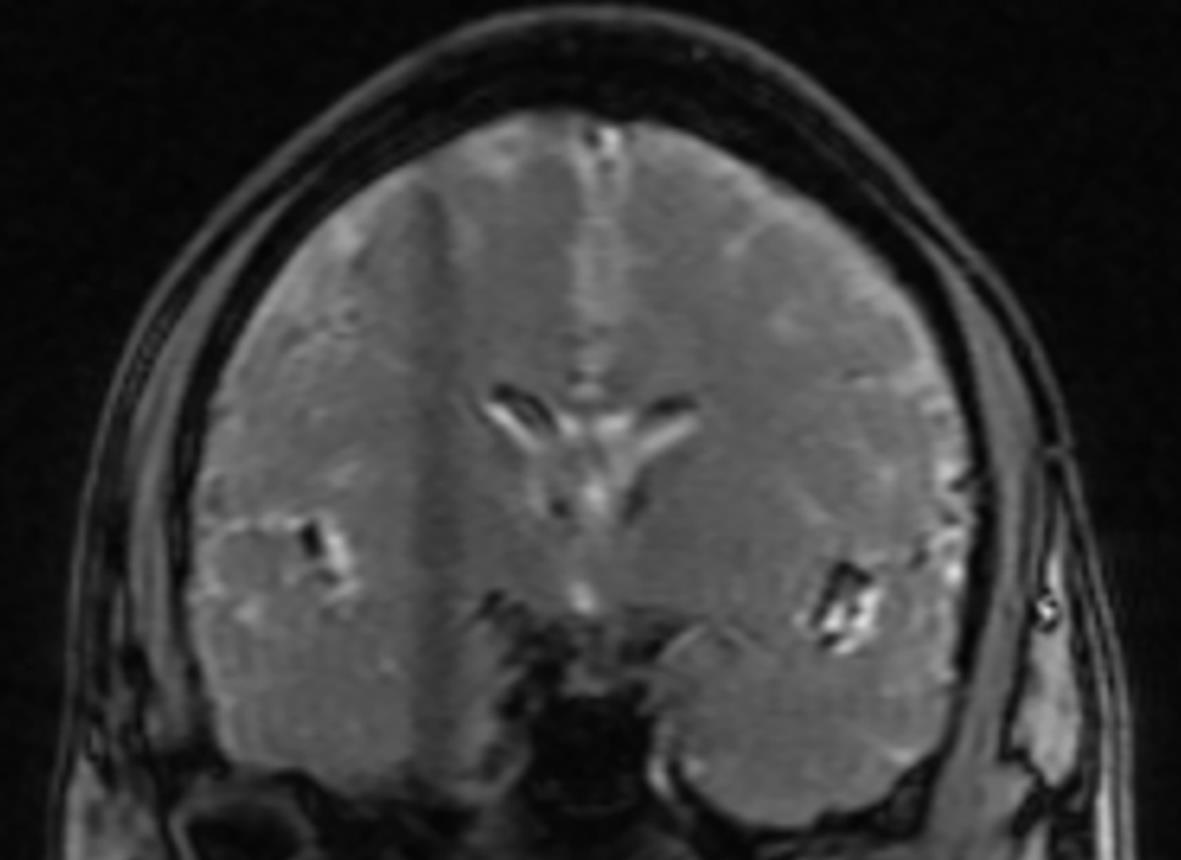

Hepatology International|3D automatic liver and spleen assessment in predicting overt hepatic encephalopathy before TIPS: a multi-center study

2024, 40(1): 128-128. DOI: 10.12449/JCH2401.gwqkjpwzjj2